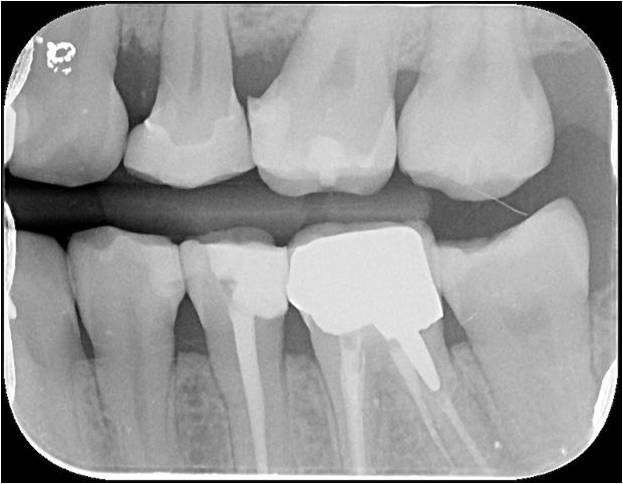

根尖片顯示邊緣密接良好